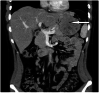

The stomach is the most common site of gastrointestinal stromal tumors (GISTs), representing 60% to 70% of all GIST tumors of the gastrointestinal tract. Gastric GISTs are usually asymptomatic discovered incidentally during endoscopic or radiological investigations. A small percentage may present with melena, hematemesis, and anemia due to recurrent bleeding. We report a case of a giant gastric GIST presented with anemia, that successfully treated with laparoscopic resection.